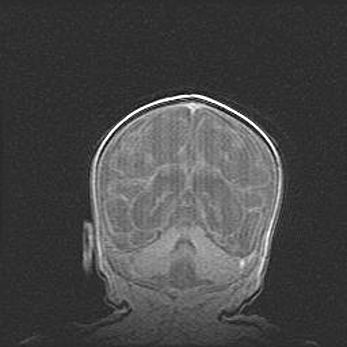

Лейкомаляция с кистозно-глиозной дегенерацией головного мозга.

Возраст: 2 месяца 25 дней

Вес: 6400 г

Окружность головы: 40 см

Срок гестации: 41 неделя

Лейкомаляцию относят к ишемически-гипоксическим повреждениям головного мозга, диагностируемым у новорожденных. При лейкомаляции в головном мозге обнаруживают очаги некроза, возникшие после тяжелой гипоксии и нарушения кровотока. В процессе морфогенеза очаги проходят три стадии: 1) развития некроза, 2) резорбции и 3) формирования глиозного рубца или кисты. Перивентрикулярная лейкомаляция (ПЛ) встречается примерно в 12% случаев среди новорожденных, обычно – у недоношенных детей, причем, частота ее зависит от массы, с которой младенец появился на свет. Наибольшее число малышей страдает лейкомаляцией, если масса при рождении 1500-2500 г.